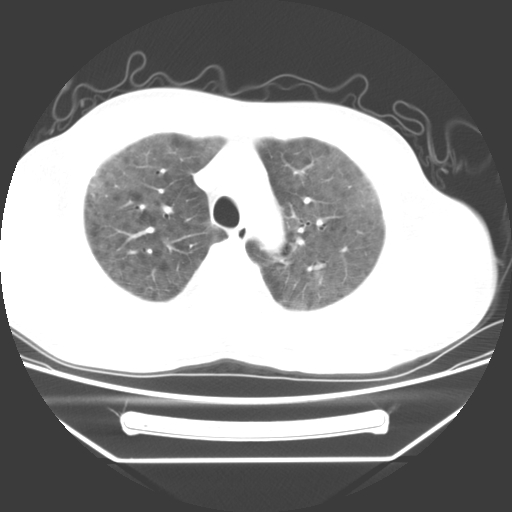

病人55岁,咳嗽,胸闷

忘了传病史了,病人55岁,咳嗽,胸闷

两肺部呈“毛玻璃”状改变,原因待查考虑感染性病变

病人是否发烧,两肺“磨玻璃”影,其间见空气支气管征和碎路石征。考虑肺泡蛋白沉着症。

两肺广泛对称磨玻璃样影,密度不均,考虑机遇性肺部感染。

双肺弥漫磨玻璃样病变,病史很重要。有感冒或发烧史,甲流不除外。无发烧可考虑肺泡蛋白沉积,但肺泡蛋白沉积边缘往往较清晰,与正常肺组织分界清晰

两肺弥漫间质性病变,考虑肺泡蛋白沉着症。建议进一步检查。